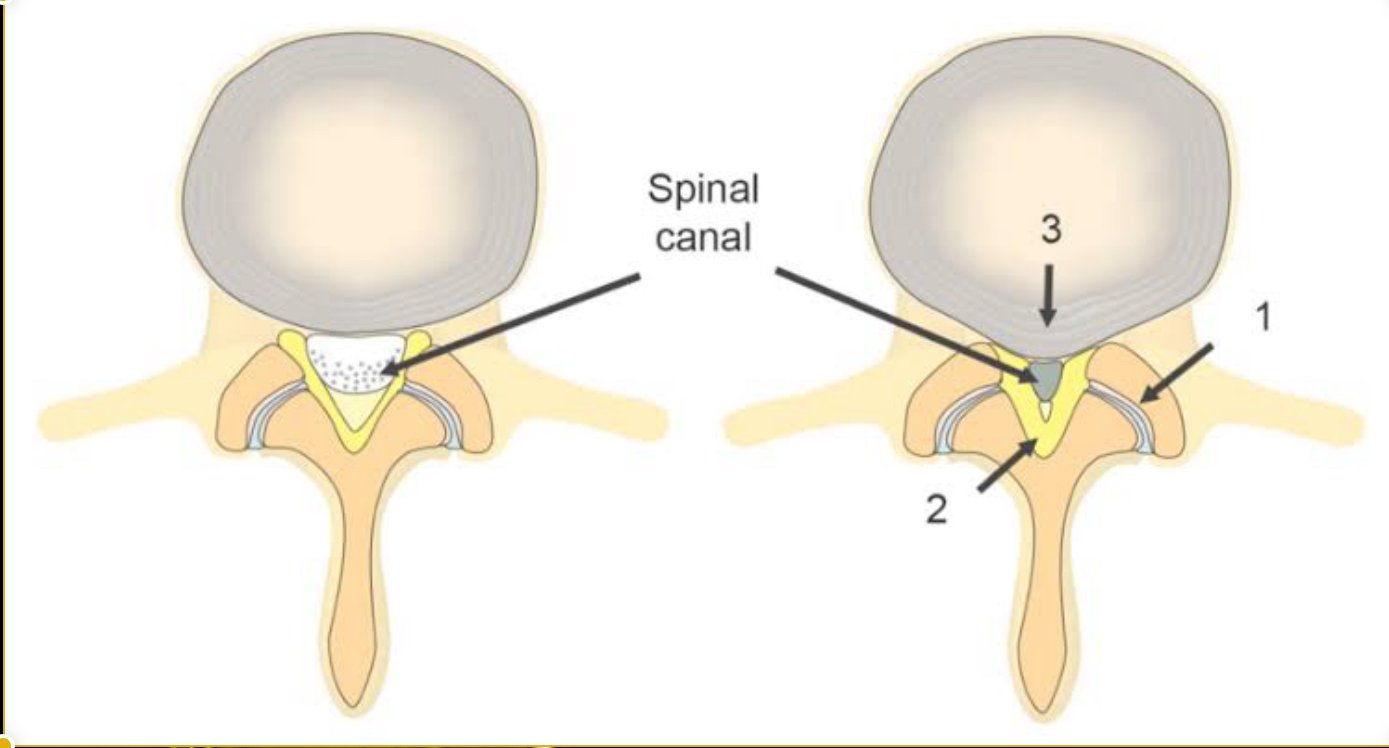

Lumbar canal narrowing usually occurs gradually and may result from one or more of the following:

- Degenerative disc bulge or disc height loss

- Thickening of spinal ligaments (ligamentum flavum hypertrophy)

- Facet joint arthritis and bone spur formation

- Degenerative spondylolisthesis

- Congenitally narrow spinal canal

- Post-surgical or post-traumatic changes